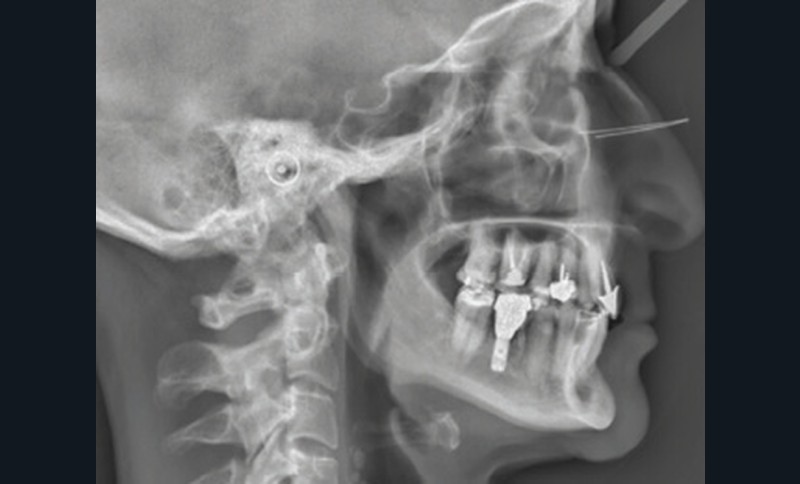

Examens complémentaires (fig. 3)

La téléradiographie de profil et l’analyse céphalométrique montrent une classe I squelettique tendance classe II dans un contexte d’hypodivergence avec diminution de l’étage masticatoire. L’axe de l’incisive mandibulaire est en normoposition, alors que l’incisive maxillaire présente une rétroalvéolie importante.

La supraclusion antérieure est d’origine mandibulaire en lien avec une courbe de Spee marquée quantifiée à 3 mm. L’orthopantomogramme confirme la présence d’un implant en 36.